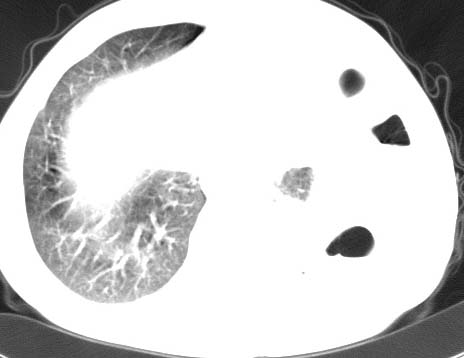

标题: CT10145:男性,30岁,活动后气促2月余.隔疝伴胸腔积液.右上肺结 [打印本页]

男性 病人 30岁,活动后气促2月余.隔疝伴胸腔积液.右上肺结核!

左侧胸腔积液,并胸腔内见多个含液 气组织,并相互重叠。影像特征很特殊,应该是“膈疝”。支持!

左侧膈疝,及左侧胸水,双上肺结核。

支持!左侧膈疝,左侧胸水,双上肺结核。

左侧胸腔包裹性液气胸未除。

左膈疝?